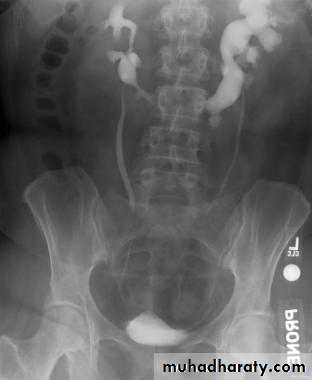

Calcification of the urinary bladder wall

bladder exstrophy

radiographic appearance in bladder exstrophy. It describes wide midline separation of the pubic bones.Bladder exstrophy (also known as ectopia vesicae) refers to a herniation of the urinary bladder through an anterior abdominal wall defect. The severity of these defects is widely variable.